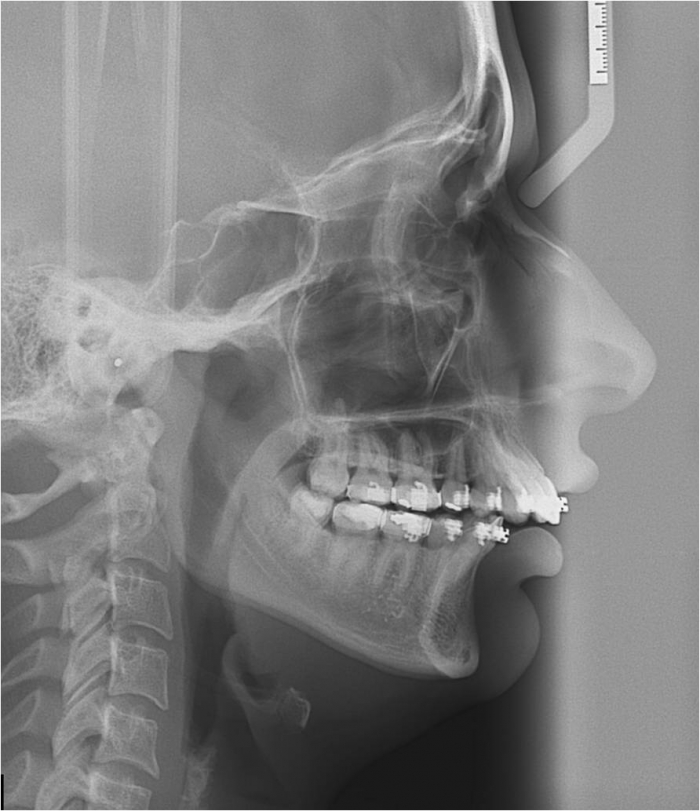

Telerradiografia após a cirurgia